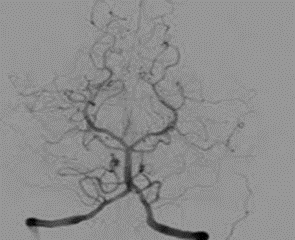

• Angiografía por contraste radiopaco

Angiografía por contraste radiopaco

Se desarrolla la angiografía por contraste radiopaco, por parte del neurólogo portugués Egas Moniz, para el diagnóstico de diferentes trastornos cerebrales.

Augusto Brandão Filho fue el pionero de los exámenes neurorradiológicos en nuestro país. Fue el primero en realizar ventriculografía y angiografía cerebral en Brasil. contó con la colaboración en ventriculografía contó con la asistencia de Manuel de Abreu futuro inventor en 1936 de la imagen fluoroscópica del cuadro, conocida como abreugrafía. En angiografía cerebral, fue asistido por el inventor del método, Egas Moniz, quien en 1928 estaba de visita en Brasil